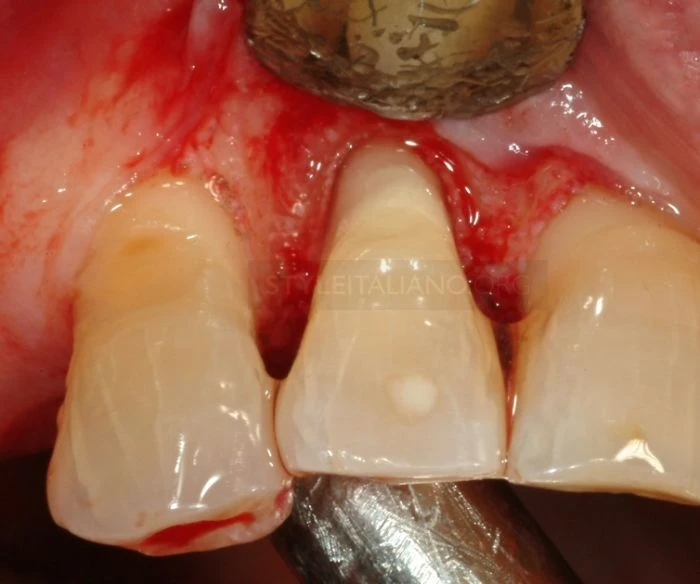

Sau khi tiến hành chuẩn đoán và tiến hành gây tê tại chỗ, các bác sĩ tiến hành nhổ mảnh răng bị gãy.

Lúc này có thể thấy được đường răng bị gãy, đây là trường hợp gãy chân răng theo phân loại mới nhất.(5)

Quan sát vết gãy: có thể thấy máu chảy nhiều hơn ở phía ngoài bởi tổn thương kéo dài hơn về chóp răng khía bên ngoài.

Chú ý quan sát có thể thấy điểm hở tủy.